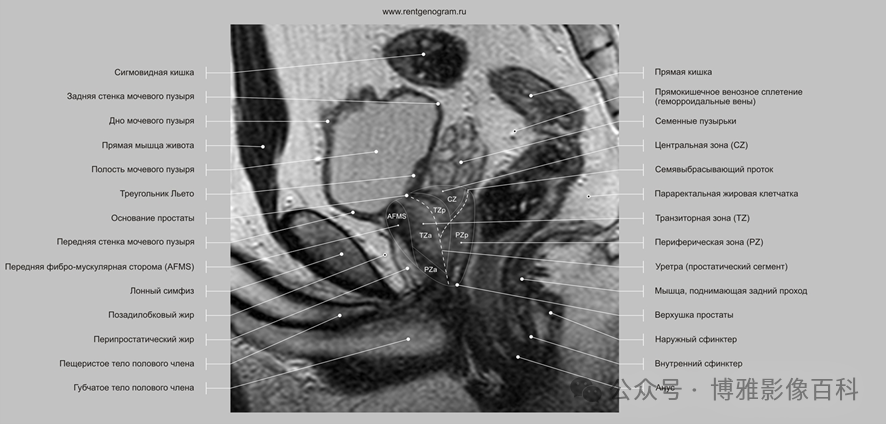

MR 解剖学

前列腺良性增生患者的轴向T2 图像,其他方面正常。外周带是一薄层均匀的高信号,边界清晰连续性的低信号包膜。移行带通常表现为不均匀中等信号,病灶被边界清楚的BPH良性前列腺增生结节所取代。精囊具有均匀T2高信号。未见淋巴结肿大。